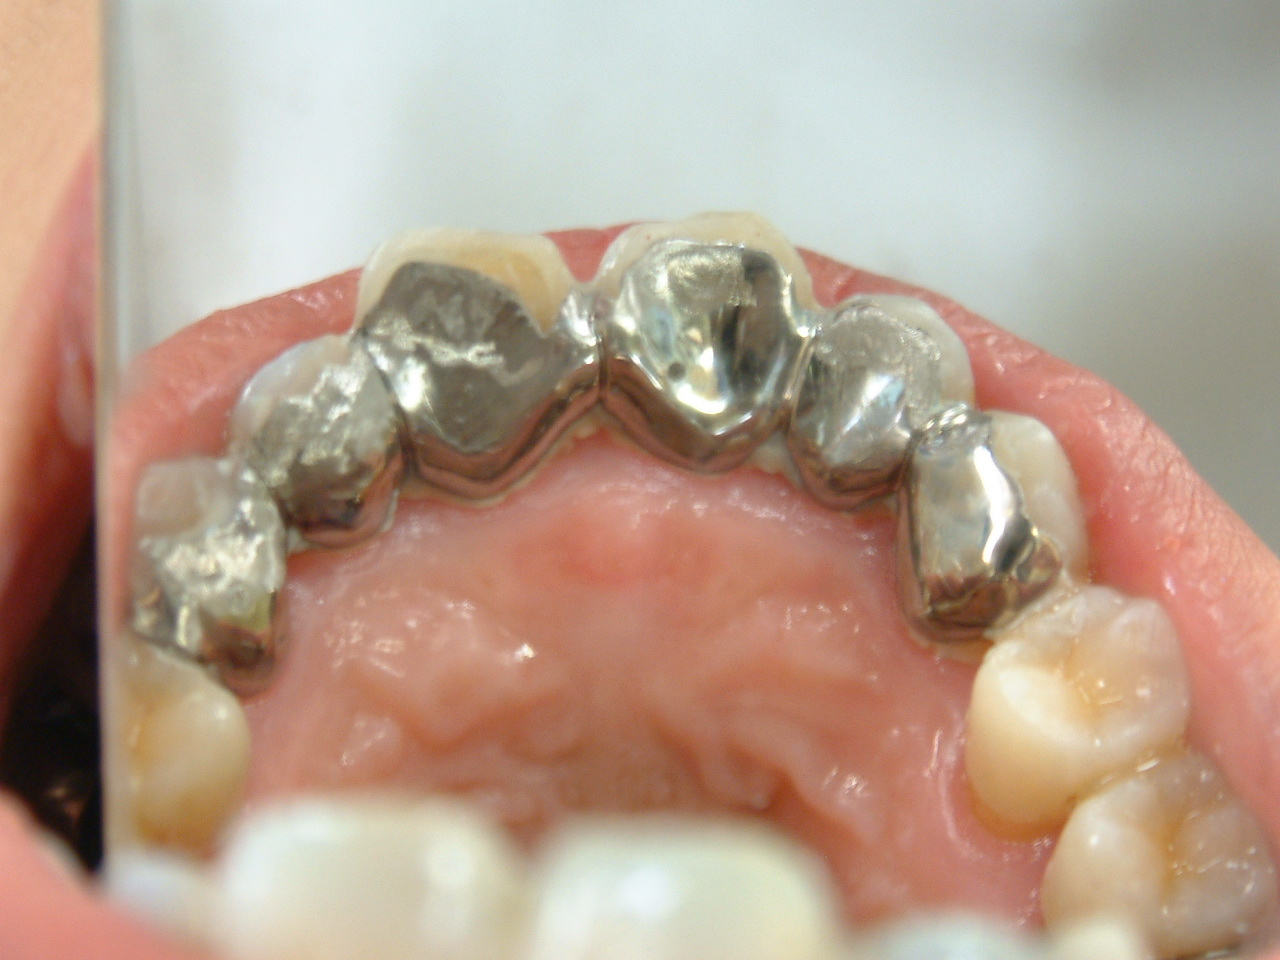

方法は各動揺歯を取り巻く歯槽骨の状態をCT撮影により観察し固定に必要な歯数を決めます。次に、これらのデータから咬合力の分散構造を設計し、使用金属として長期間の金属疲労に耐える白金加金を選びます。

また、中高年では歯の咬み合わせの面(咬合面)が摩耗している場合が多いため歯の削除量を慎重に決めると共に、切削時にはレーザー照射によって切削面を知覚過敏から保護します。病状が進行している例では歯列の乱れによって歯の切削だけでなく、技工製作においても極めて精度の高い技術と技能が必要になります。

7-5.動揺歯固定装置による効果

- 安定して咀嚼することができます。

- 歯槽骨の吸収がとまります。

- 歯の動揺による歯周ポケットへの細菌侵入が防止できます。

7-6.動揺歯固定装置

以下に動揺歯固定装置の具体例を示します。